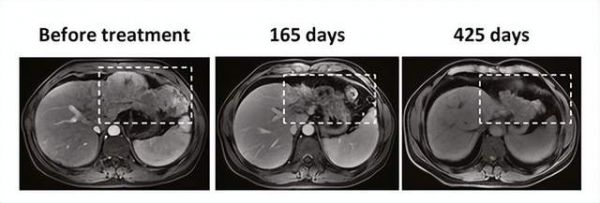

值得注意的是,该试验中1例脂肪肉瘤患者,在TCR-T细胞TAEST16001治疗后实现部分缓解,并持续缓解超1年!

截图来源于参考资料4,侵权请联系删除

其中1例患者在治疗165天后,肿瘤显著坏死,425 天后,肿瘤明显减小。

截图来源于参考资料5,侵权请联系删除